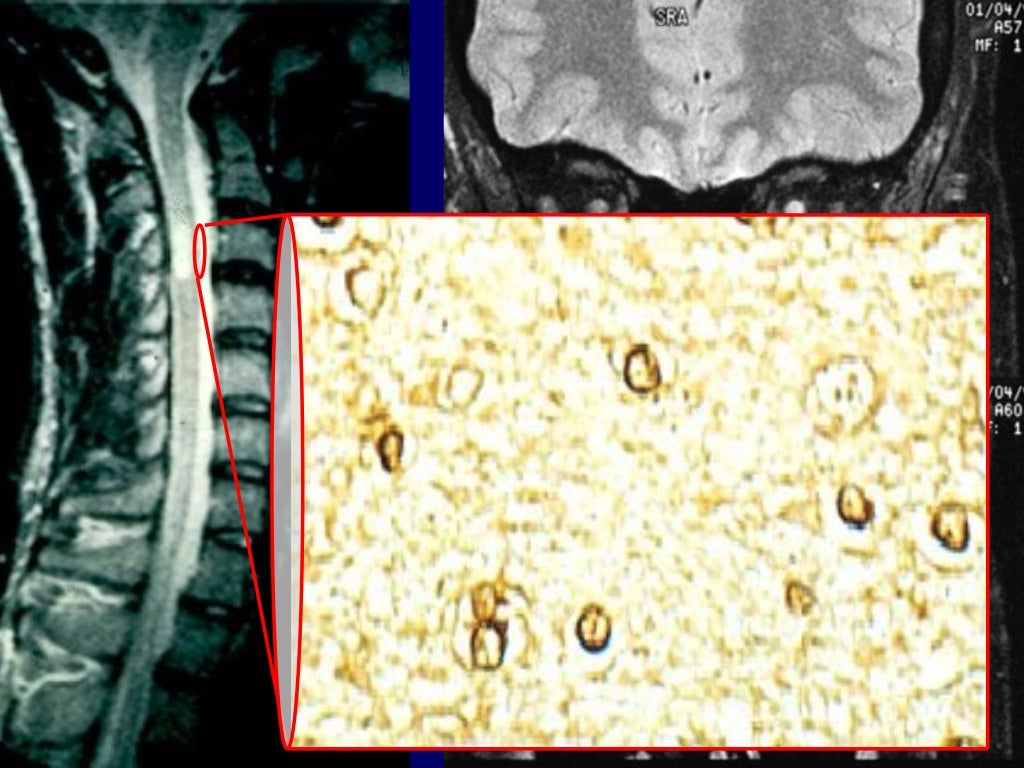

He still has those disabilities so he can't really walk any distance. Wife Alison found out about the groundbreaking treatment and the couple have gone on to set up a charity for people living with MSĪlison said: "James is medically retired now. The couple have also set up the Aims charity to raise awareness of the treatment and offer support to people with MS. The treatment’s allowed James and Alison to travel the world and make plans for the future, they hope others will now get the chance to fulfil their dreams as well. "It's important that we establish the exact place of stem cell transplantation in the therapeutic armamentarium of MS in the modern era - that is why we are comparing stem cell transplantation with the modern drugs that are currently available and licensed for use in MS." He said: “Autologous hematopoietic stem cell transplantation has been shown to be highly effective in stabilising, and even reversing disability, in certain patients with multiple sclerosis.” Credit: ITV GranadaĬhief trial investigator Prof John Snowden, a Consultant Haematologist at Sheffield Teaching Hospitals, said the study may also provide insights into immune system abnormalities that cause the disease. In MS, the immune system attacks the nerves, causing inflammation that affects the brain and spinal cord. Researchers say the £2.3 million study could soon lead to patients with aggressive MS being offered the transplant as a first-line treatment, instead of only when other treatments have failed. The world-first StarMS study, which has two specialist units in Liverpool and Salford, could offer new hope for people with aggressive forms of MS. It is currently incurable, and until recently, treatment has mainly used drugs that reduce the worst symptoms but do not halt the disease. It affects 100,000 Brits, and can lead to life in a wheelchair. Stem cells are used to repopulate the bone marrow to make new cells, which “reboots” the immune system. Credit: ITV GranadaĪutologous hematopoietic stem cell transplantation, or AHSCT, involves harvesting the patients’ blood and bone marrow stem cells before stripping the body’s immune system using chemotherapy.